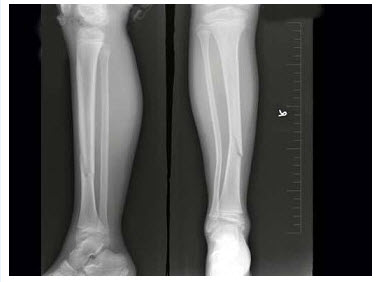

93、单项选择题

男,16岁,左小腿上端疼痛3个月余,局部肿胀,皮温稍高。结合左胫腓骨正侧位片,最可能的诊断为()

A.急性化脓性骨髓炎

B.骨化性肌炎

C.骨肉瘤

D.成软骨细胞瘤

E.软骨肉瘤